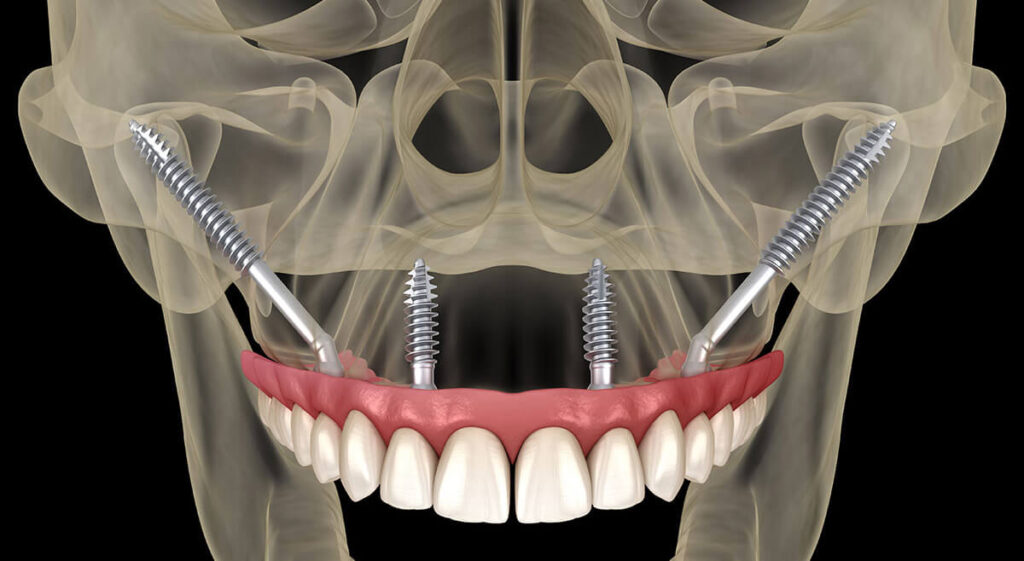

Zygomatic implants are a specialized solution for patients with severe bone loss in the upper jaw. Unlike traditional implants that are anchored in the jawbone, zygomatic implants are longer and anchored in the dense zygomatic (cheek) bone. The zygomatic bone is naturally denser and stronger than the jawbone, making these implants highly durable and reliable over time. This procedure allows for implant treatment without the need for additional procedures like bone grafting or sinus lifts, which means patients can avoid additional surgical operation, significantly shortening the overall treatment time.

Unlike traditional implants, zygomatic implants:

Are longer in structure,

Are designed to fit the facial bone anatomy,

Provide a stable foundation for dental prosthetics in patients with severe bone loss.